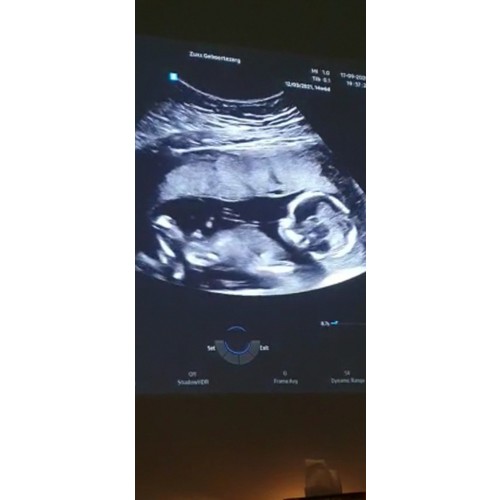

Bij 13w en 5 dagen zag je het ook vanaf zijkant en deze echo is 14w en 6 dagen

Ik was daar 14 weken en 6 dagen😊

Dit is mijn echo foto van vandaag, mijn vriendinnen heb ik een envelop gegeven met het geslacht en ik weet het zelf ook niet. Vraag me ook af of mensen het geslacht kunnen zien na aanleiding van deze echo.